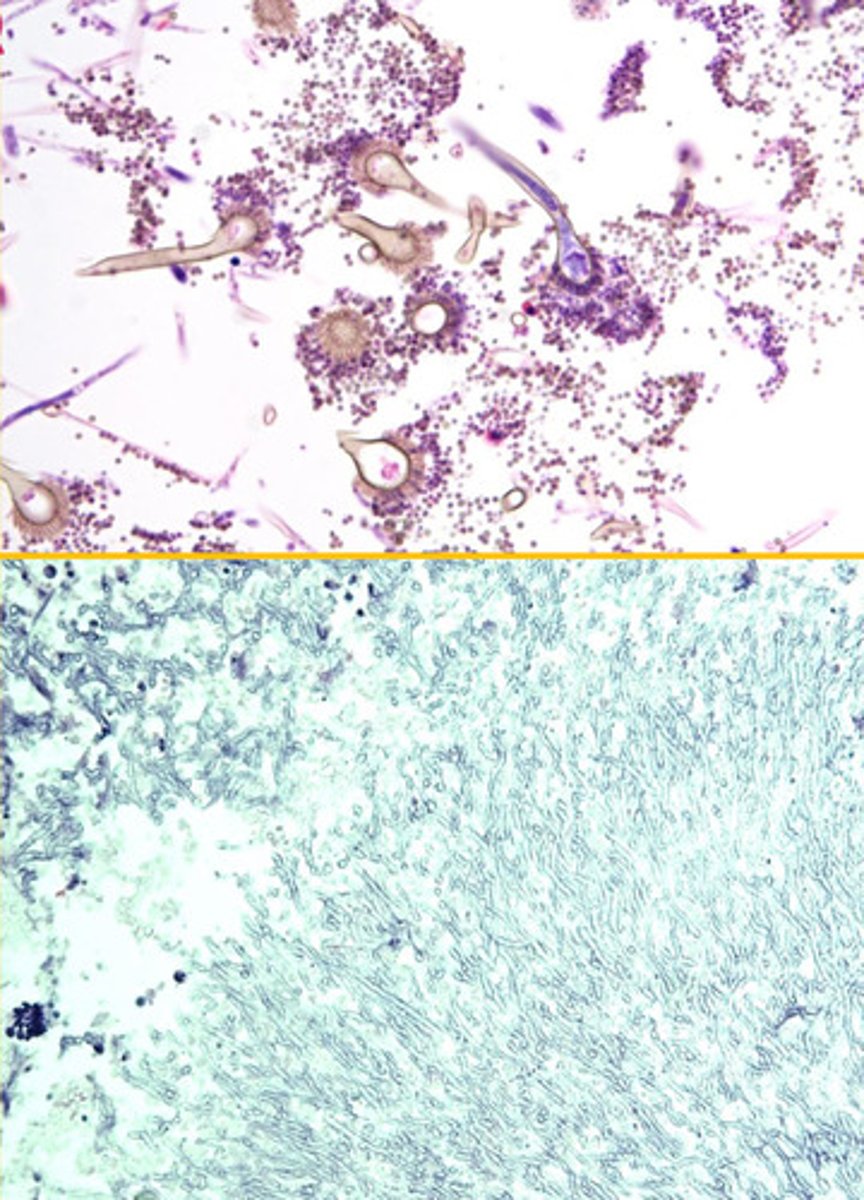

Cryptococcus

Identify the pathogen?

Mucicarmine stain

What stain is used to see Cryptococcus?